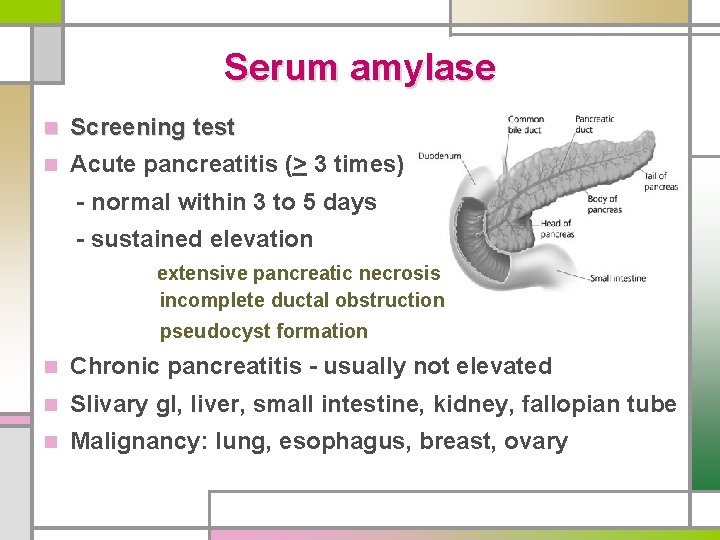

Serum amylase n Screening test n Acute pancreatitis (> 3 times) - normal within 3 to 5 days - sustained elevation extensive pancreatic necrosis incomplete ductal obstruction pseudocyst formation n Chronic pancreatitis - usually not elevated n Slivary gl, liver, small intestine, kidney, fallopian tube n Malignancy: lung, esophagus, breast, ovary

Table 303 -2. Causes of Hyperamylasemia and Hyperamylasuria PANCREATIC DISEASE NONPANCREATIC DISORDERS I. Pancreatitis I. Renal insufficiency A. Acute II. Salivary gland lesions B. Chronic: ductal obstruction A. Mumps C. Complications of pancreatitis B. Calculus 1. Pancreatic pseudocyst C. Irradiation sialadenitis 2. Pancreatogenous ascites D. Maxillofacial surgery 3. Pancreatic abscess III. "Tumor" hyperamylasemia 4. Pancreatic necrosis A. Carcinoma of the lung II. Pancreatic trauma B. Carcinoma of the esophagus III. Pancreatic carcinoma OTHER ABDOMINAL DISORDERS C. Breast CA, ovarian CA IV. Macroamylasemia I. Biliary tract disease: cholecystitis, choledocholithiasis V. Burns II. Intraabdominal disease VI. Diabetic ketoacidosis A. Perforated or penetrating peptic ulcer VII. Pregnancy B. Intestinal obstruction or infarction VIII. Renal transplantation C. Ruptured ectopic pregnancy IX. Cerebral trauma D. Peritonitis X. Drugs: morphine E. Aortic aneurysm F. Chronic liver disease G. Postoperative hyperamylasemia